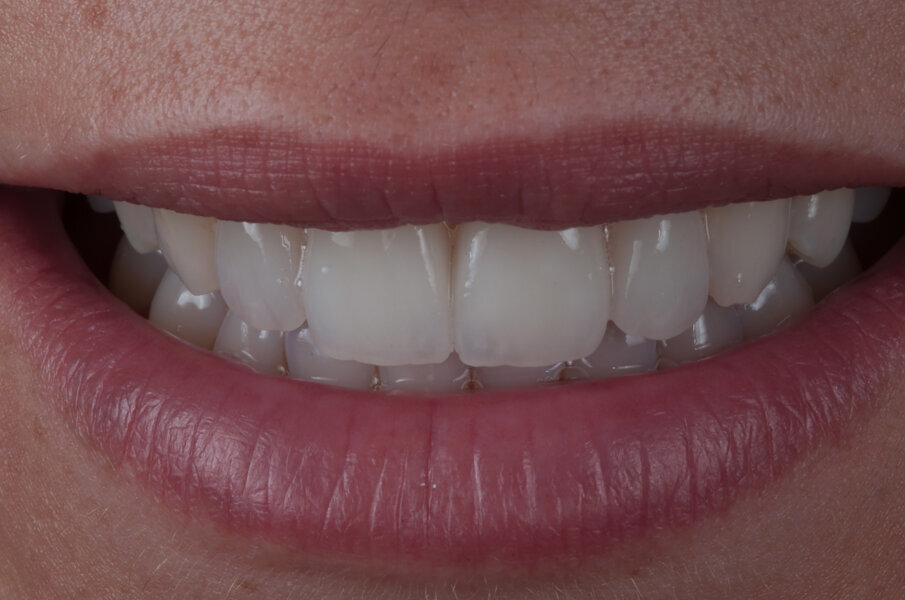

Figg. 20-23 - Restauro definitivo con tutti i dettagli della texture sui restauri in bocca.